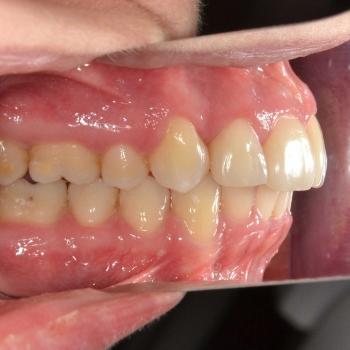

A kezelés végére minden problémát sikerült megoldanunk, a középvonalak korrekcióját leszámítva. Ennek ellenére, mivel a felső középvonal az arc tengelyében helyezkedik el, az esztétikai eredmény nem csorbult és a funkciót sem befolyásolta. A jobb alsó 6-os fog implantációs pótlása a fogszabályozás befejeztével kezdődött meg.

A kezelés időtartama: 2 év 6 hónap